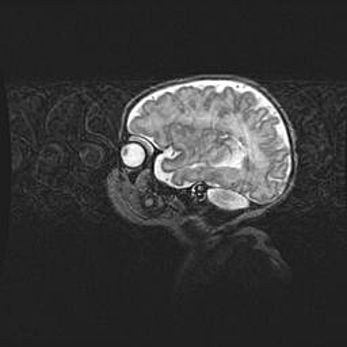

Аномалия Денди-Уокера. Признаки гипоплазии мозолистого тела.

Возраст: 5 месяцев 3 дня

Вес: 5550 г

Пол: мужской

Окружность головы: 39 см

Срок гестации: 40 недель

Аномалия Денди-Уокера – это порок развития головного мозга, для которого характерна триада симптомов: гипотрофия или аплазия червя мозжечка и/или полушарий мозжечка, расширение четвёртого желудочка с формированием ликворной кисты задней черепной ямки, гипертензионная гидроцефалия различной степени.

Гипоплазия мозолистого тела относится к дефектам внутриутробного этапа развития мозговой ткани, возникающим в процессе закладки структур головного мозга, что происходит на начальных этапах развития эмбриона.